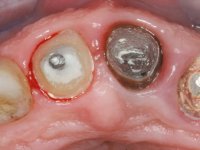

Endodontic treatments were performed and a metalic non screwed intra radicular post was placed on tooth 1.1. An alginate impression was made for laboratory confection of a reinforced acrylic provisional bridge, with teeth 1.1 and 2.2 as abutments and 2.2 as a pontic. After preparation of tooth 1.1 and root preparation of 2.1, the bridge was relined in mouth with self-polymerizable acrylic using a metal post for further retaining the prepared root canal on 2.1. Tooth 2.2 was cut at the gingival level to function as support. In the same session, the impression of the root canal of the 2.1 was made for the laboratory confection of a cast post and core. A double mixture technique with plastic tutor was used after previous canal vaseline with endodontic file and cotton. The provisional bridge was provisionally cemented and the cast post and core was made in the laboratory. Cast post and core cementation was made with resin-reinforced glass ionomer cement and the provisional bridge had to be readjusted to the new situation by removing the post at the site of 2.1. After careful surgical planning, a dental implant was placed, simultaneously with extraction of the root of tooth 2.2. The provisional bridge was placed by resting on the healing screw placed in the implant. The respected osteointegration period was 12 weeks, during which the provisional bridge was relined twice. After complete maturation of hard and soft tissues, definitive impressions were made. The gingival retraction technique was applied with an impregnated retraction cord and impression was performed using double mixture, open tray impression technique. A custom precious metal abutment implant was prepared in the lab, along with 3 metal caps to be used as infrastructures for the metal ceramic crowns. Particular care was taken in the confection of the cervical finishing line of the implant abutment, in order to follow the soft tissues emergence profile. Proof of infrastructures was done in the mouth being evaluated clinically and imagiologically. Collection of color information was done by the ceramist at the office. Ceramic was applied in the laboratory and the finished work was placed in the mouth after approval by the patient. Definitive cementation was made with resin-reinforced glass ionomer cement, and the first crown to be cemented was that of the implant, to facilitate removal of the excess.